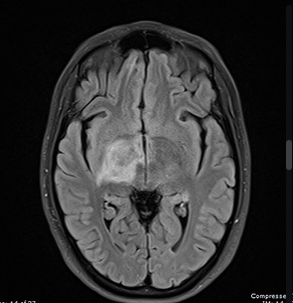

This diagnosis should be highly suspected for an individual with a brain MRI showing:

"T2 hyperintensity that extends from the thalamus caudally to the ipsilateral midbrain" (Cascade Sign).

What is Neuro-Behcet's Disease.